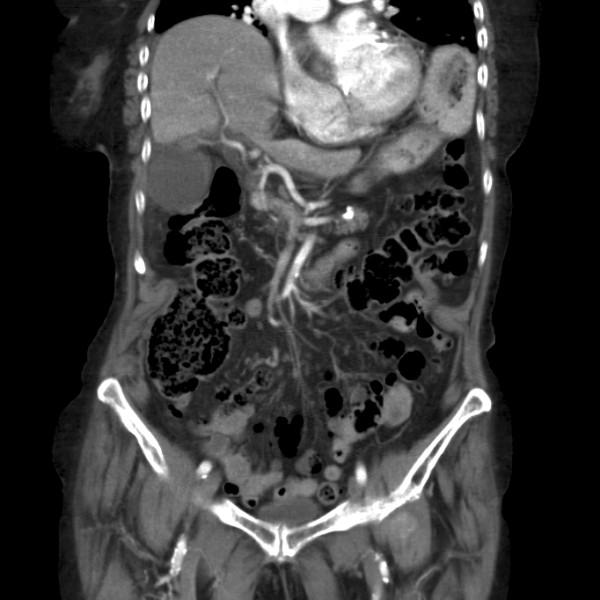

We describe the case of an 89-year-old Caucasian woman who presented with clinical symptoms suggestive of acute cholecystitis to our hospital. Radiological imaging confirmed our clinical diagnosis. At first we considered percutaneous gallbladder drainage because of her age and comorbidity, but instead performed laparoscopic cholecystectomy because of rapid clinical deterioration. During laparoscopy a necrotic gallbladder due to torsion of the gallbladder around the cystic duct was found.

我们描述了一名89岁白种女性的病例,她因出现提示急性胆囊炎的临床症状前来我院就诊。影像学检查证实了我们的临床诊断。起初,由于她的年龄和合并症,我们考虑进行经皮胆囊引流,但由于临床症状迅速恶化,我们改为进行腹腔镜胆囊切除术。在腹腔镜检查中,发现胆囊因围绕胆囊管扭转而坏死。